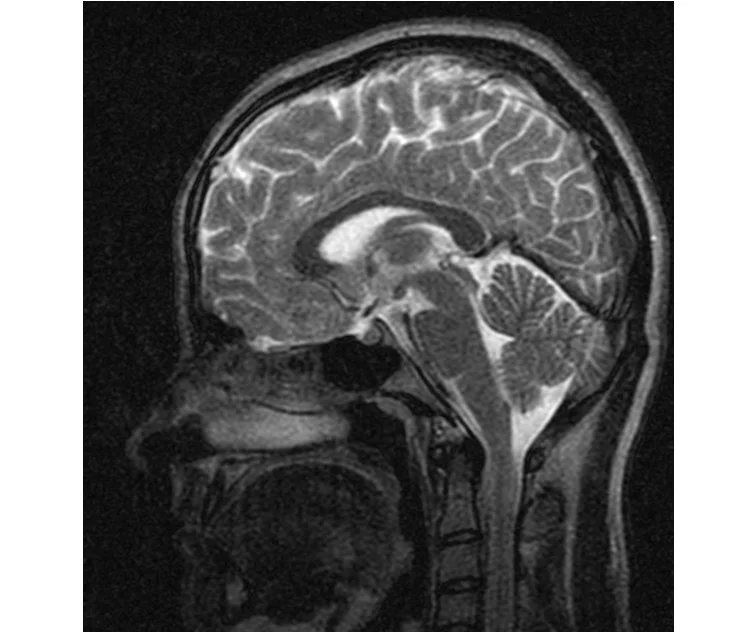

глянте на снимки томографии плиз

делал в обласной на siemense.В заключении выданом мне через 15мин.после мрт (легкая дегидрация)

Меня смутил факт выдачи заключения через 10мин(наверно они у них зарание напечатаные)я не медик.достаточно мимолётного взгляда на снимки?А вы видете на них гидроцефалию? Я лиш спросил куда идти с результатами томографии?и не хотел никого роздражать.

Я попросил взглянуть на снимки и сказать видна.ли на них гидроцефалия?или куда обратится за консультацией по этому вопросу?В мрт снимках наверно розбирается любой нервопатолог(я так предположил)

Я уже говорил, что независимо от того, есть на МРТ гидроцефалия или нет, лечиться тебе нужно только в том случае, если есть какие-либо проявления болезни, иначе на все эти анализы можешь забить... Но давай все-таки разберемся с томограммой.

Итак, с самого начала томограмма обозначала срез какого-либо органа на определенной глубине, позволяла заглянуть вовнутрь. При компьютерной томографии аппарат делает десятки срезов головного мозга в разных направлениях и из этого множества срезов он моделирует полноценное объемное изображение мозга в натуральную величину. Обрати внимание, компьютер работает не с этими миниатюрными изображениями, а с трехмерной моделью в масштабе 1:1. Эту модель вдоль и поперек анализирует суперсовременный компьютер, выполняющий миллионы операций в секунду. Только ***** может пытаться перепроверить компьютер, ведь человеку не хватит всей жизни чтобы проанализировать то, что компьютер с тобой сделал за 10 минут. Я хочу, чтобы ты это понял!

Ты разместл здесь несколько миниатюр и хочешь, чтобы врач по ним создал полноценное объемное изображение в натуральную величину, а потом осмотрел его со всех сторон и дал заключение? Но ведь это невозможно. Это просто насмешка над врачом, это издевательство над здравым смыслом. Принеси Букеру уменьшенный в 50 раз снимок зуба и спроси у него, в каком состоянии там корневые каналы. Или давай я дам тебе скрин со спутниковой карты города и попрошу тебя описать, какого цвета и какой модели запечатленная со спутника машина, какой у нее гос.номер, сколько в ней пассажиров, сколько из них мужчин и сколько женщин...